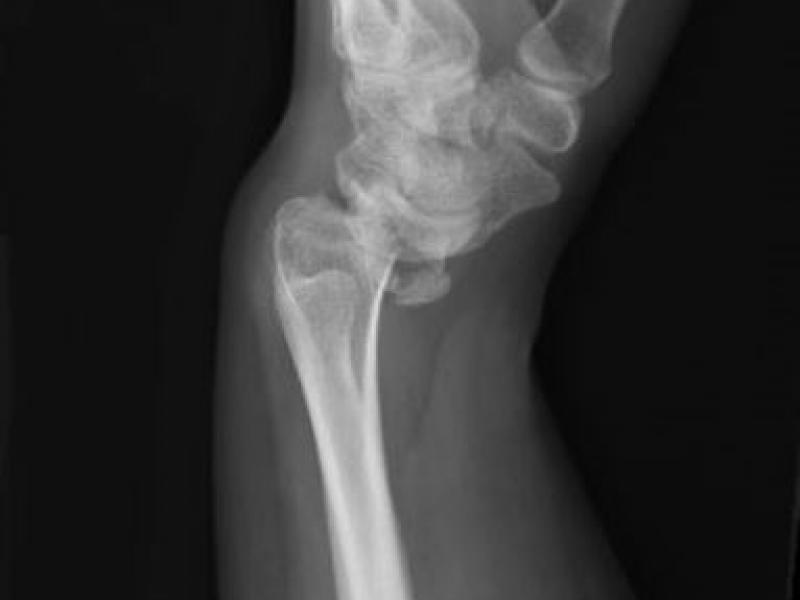

What's the Diagnosis? By Dr. Patrice Baptista

29 y/o female presents to the ED w/ L wrist pain. She is s/p